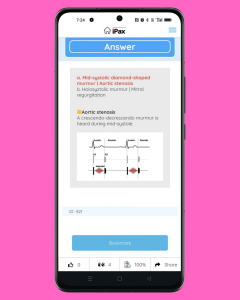

On May 4, the quiz involves listening to two heart murmurs and selecting the matching phonocardiogram. It is necessary to distinguish between a mid-systolic murmur and a holosystolic murmur. (May 4, 2025)

On May 4, the quiz involves listening to two heart murmurs and selecting the matching phonocardiogram. It is necessary to distinguish between a mid-systolic murmur and a holosystolic murmur.

5月4日は2つの心雑音を聴いて心音図に一致するものを選ぶ問題です。収縮中期雑音と全収縮期雑音を聴き分ける必要があります。